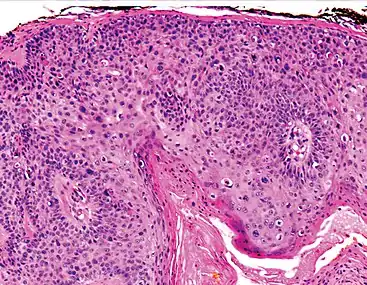

Invasive disease

In invasive cSCC, tumor cells infiltrate through the basement membrane. The infiltrate can be somewhat difficult to detect in the early stages of invasion: however, additional indicators such as full thickness epidermal atypia and the involvement of hair follicles can be used to facilitate the diagnosis. Later stages of invasion are characterized by the formation of nests of atypical tumor cells in the dermis, often with a corresponding inflammatory infiltrate.[12]

Superficially invasive cutaneous squamous-cell carcinoma. These lesions often do not show the marked pleomorphism and atypical nuclei of cSCC in situ, but manifest early keratinocyte invasion of the dermis.[12]

High magnification demonstrates the pleomorphism of the invading keratinocytes[12]

Invasive nests with characteristic large celled centers. Ulceration (at left) is common in invasive cSCC.